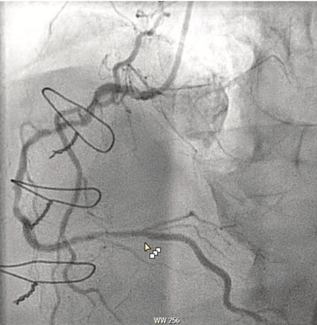

We describe a case of a right coronary artery (RCA) perforation that was successfully treated using a polyurethane-coated (PK Papyrus) stent (Biotronik).